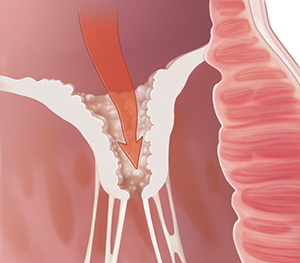

Problems opening (stenosis)

When a valve doesn’t open all the way, the problem is called stenosis. The leaflets may be stuck together or too stiff to open fully. When the valve doesn’t open fully, blood has to flow through a smaller opening. So the heart muscle has to work harder to push the blood through the valve.

|

| Stenosis. |